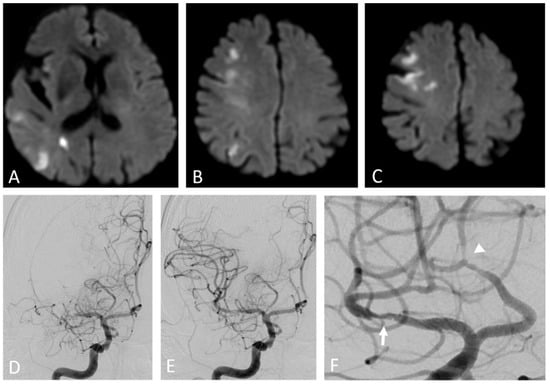

Figure 3.

Artery-to-artery embolism and in situ thrombotic occlusion of the middle cerebral artery due to intracranial atherosclerotic disease. Hypertensive 67-year-old man. Diffusion-weighted magnetic resonance imaging demonstrates multiple cortical-subcortical ischemic lesions in the territory of the right middle cerebral artery (A–C). Digital subtraction angiography shows an occlusion of the M1 segment of the right middle cerebral artery (D) and its complete recanalization after mechanical thrombectomy (E). The magnified oblique projection after the recanalization (F) reveals an underlying atherosclerotic plaque at the site of the previous occlusion (arrow) and additional stenotic lesions along the course of the right anterior cerebral artery (arrowhead).